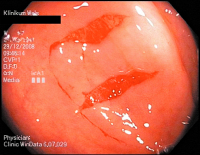

Kollagene Kolitis

Abbildung 4: Schleimhautlängsrisse im Sigma bei kollagener Kolitis im Rahmen der Koloskopie.